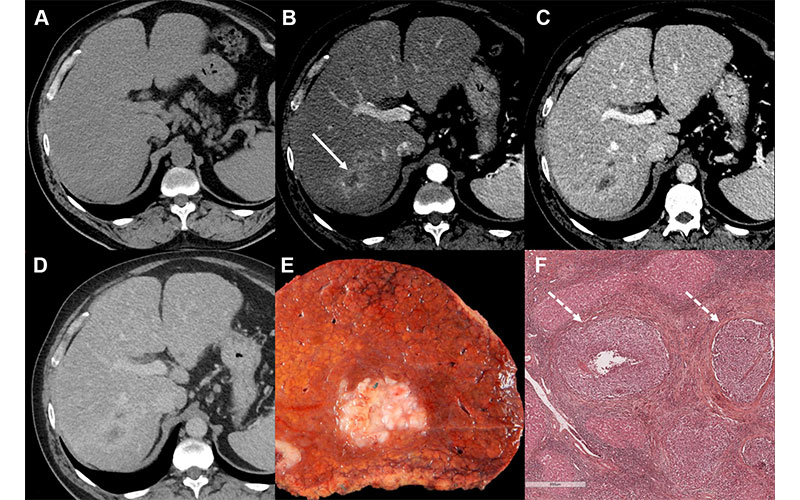

Images in a 55-year-old male patient with a history of hepatitis C virus–related cirrhosis and a 45-mm hepatocellular carcinoma (HCC). Axial (A) precontrast and (B–D) contrast-enhanced CT images in the (B) hepatic arterial, (C) portal venous, and (D) delayed phases show lesion (arrow in B) with rim arterial phase hyperenhancement categorized as Liver Imaging Reporting and Data System category LR-M. (E) Photograph of resected specimen shows a poorly demarcated HCC. (F) Photomicrograph (hematoxylin-eosin stain) reveals a poorly differentiated HCC with microvascular invasion (arrows). Scale bar in F = 600 µm. Intrahepatic recurrence was observed at 14 months after resection. https://doi.org/10.1148/radiol.231160 ©RSNA 2024